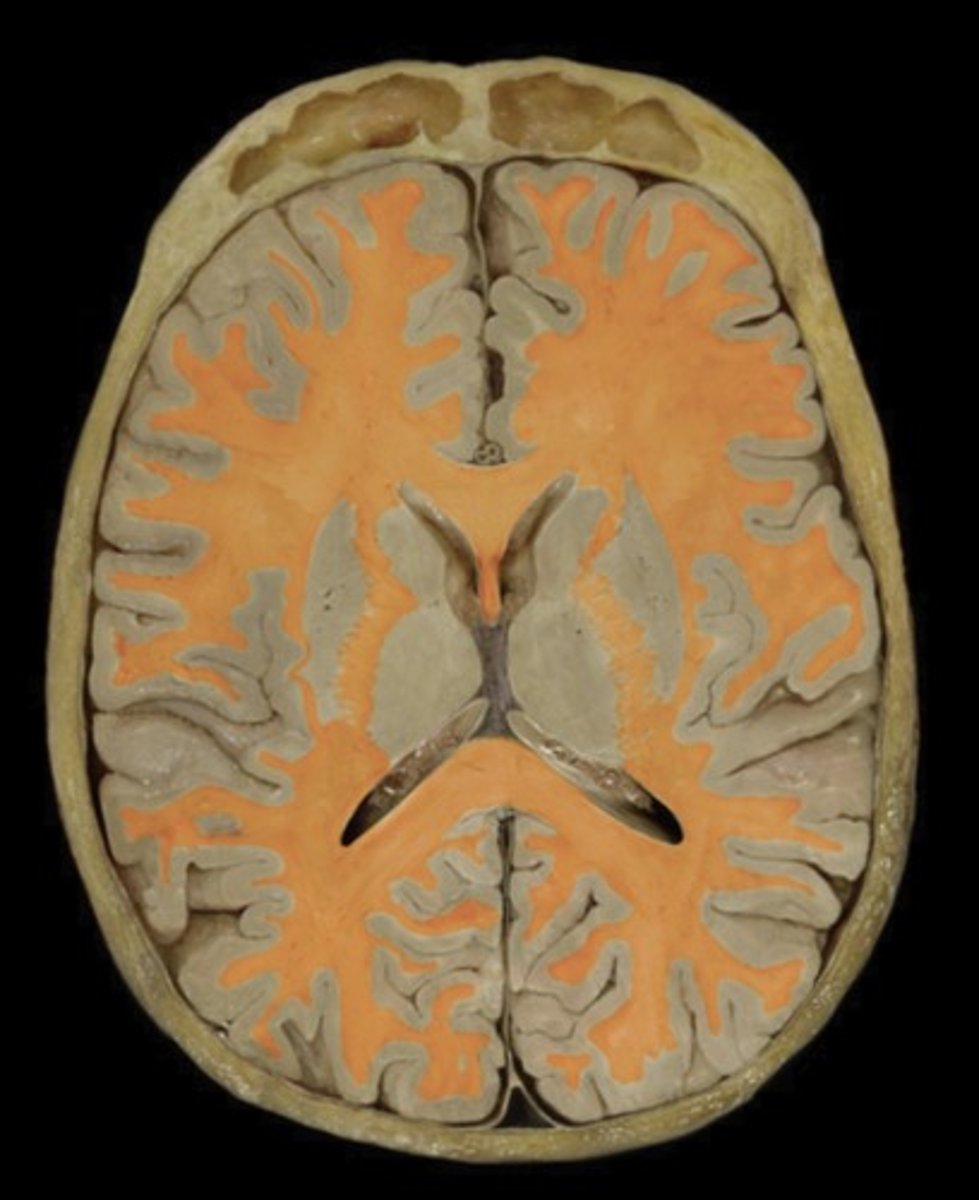

White matter

Name this structure

Gray matter

Name this structure

Occipital Lobe (transverse section)

Name this structure

Temporal Lobe (transverse section)

Name this structure